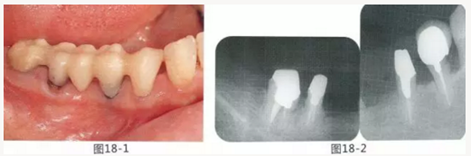

圖18-1 右上4,5,6,6,7部位,初期治療結束時牙齦的狀態(tài)。

圖18-2 手術前同部位的口腔X光片。